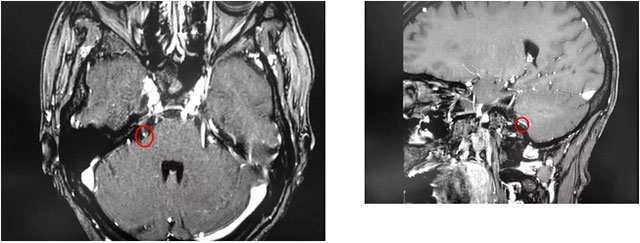

▲ 患者右側(cè)三叉神經(jīng)與周圍小血管關(guān)系密切

最近,金女士慕名來到上海藍(lán)十字腦科醫(yī)院尋求進(jìn)一步治療。沈建康教授和醫(yī)院神經(jīng)外科6B病區(qū)潘仁龍主任團(tuán)隊結(jié)合患者病史和影像學(xué)分析,判斷患者右側(cè)三叉神經(jīng)與周圍小血管關(guān)系密切,經(jīng)開展嚴(yán)謹(jǐn)?shù)脑u估討論并取得家屬同意后,沈建康教授為金女士開展了微血管減壓手術(shù)。

術(shù)中,借助先進(jìn)的蔡司顯微鏡(雙熒光)設(shè)備,沈教授牽開患者腦組織,顯露三叉神經(jīng),見神經(jīng)近基底處有小腦前動脈分支于后方穿行而過。沈教授小心翼翼地分離二者,將三叉神經(jīng)近基底處及動脈穿行處填塞特氟龍墊片分隔。